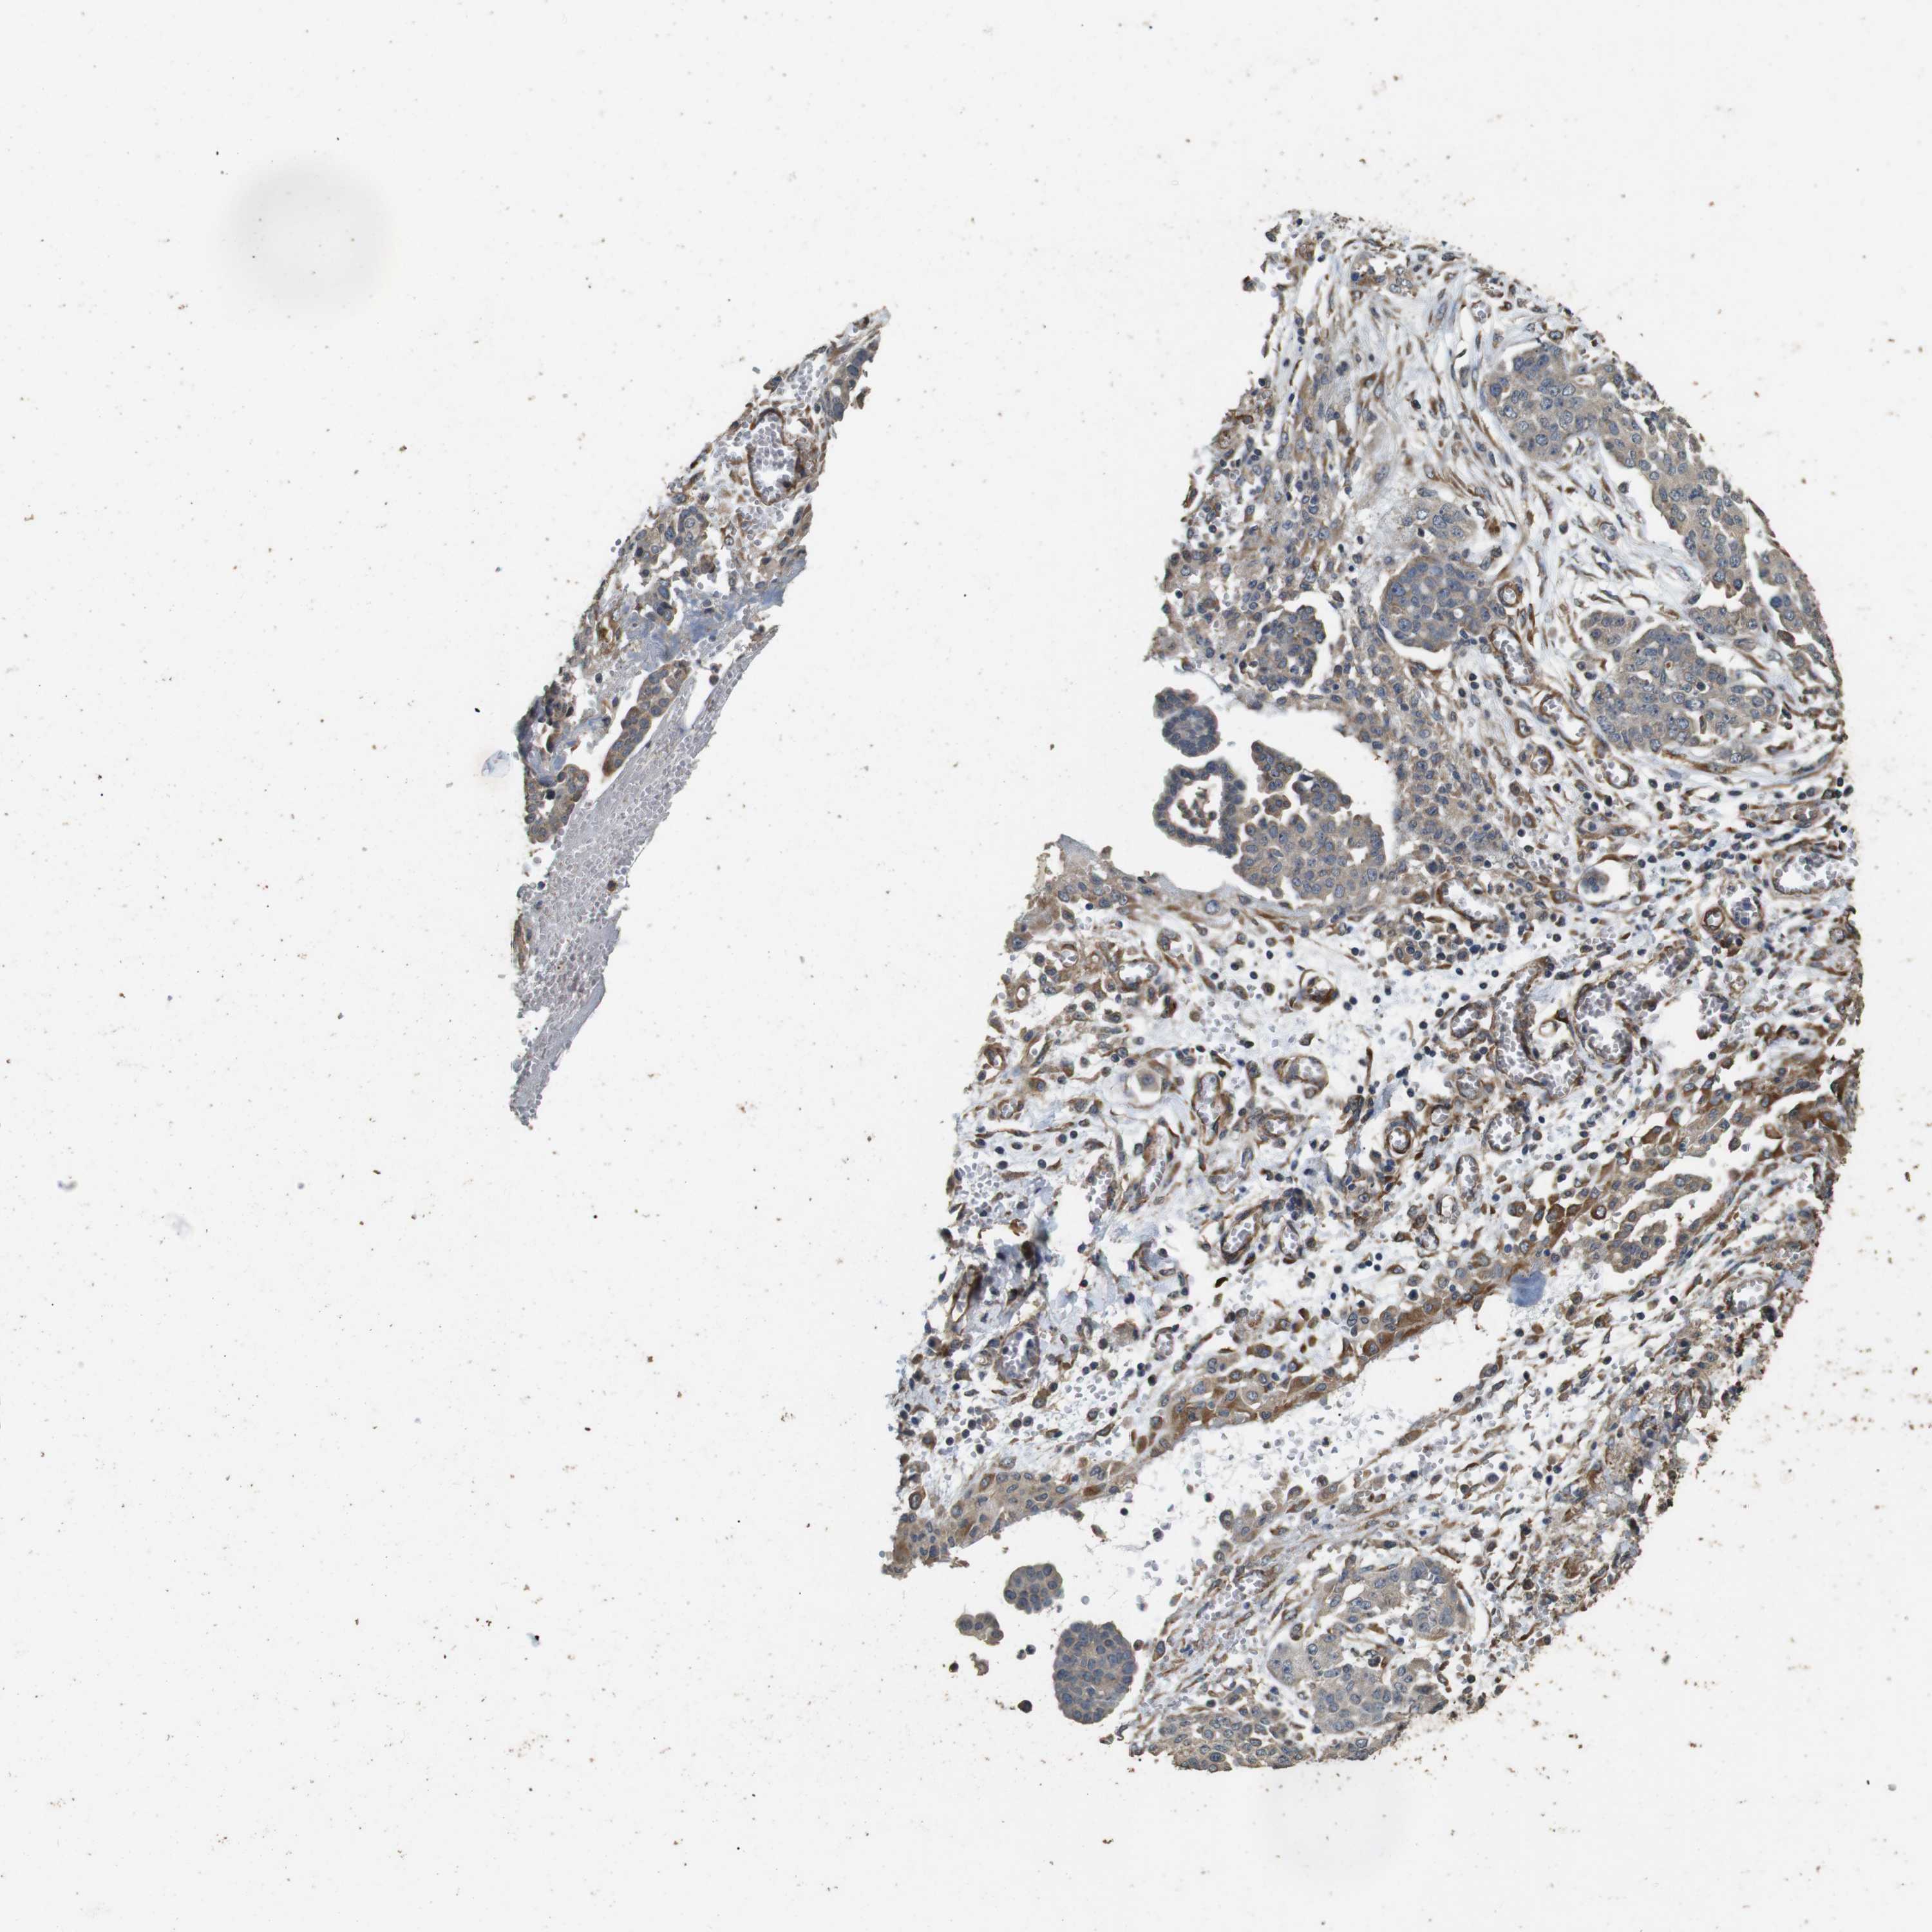

OVARIAN CANCER - Protein expressioni

A mouse-over function shows sample information and annotation data. Click on an image to view it in a full screen mode. Samples can be filtered based on level of antibody staining by selecting one or several of the following categories: high, medium, low and not detected. The assay and annotation is described here.

Note that samples used for immunohistochemistry by the Human Protein Atlas do not correspond to samples in the TCGA dataset.

Antibody stainingi

Antibody staining in the annotated cell types in the current human tissue is reported as not detected, low, medium, or high, based on conventional immunohistochemistry profiling in selected tissues. This score is based on the combination of the staining intensity and fraction of stained cells.

Each image is clickable and will lead to virtual microscopy that enables deeper exploration of all samples and also displays staining intensity scores, fraction scores and subcellular localization as well as patient and tissue information for each sample.

Antibody HPA014166

Antibody HPA025240

Cystadenocarcinoma, serous, NOS

Carcinoma, endometroid

Cystadenocarcinoma, mucinous, NOS

Carcinoma, NOS